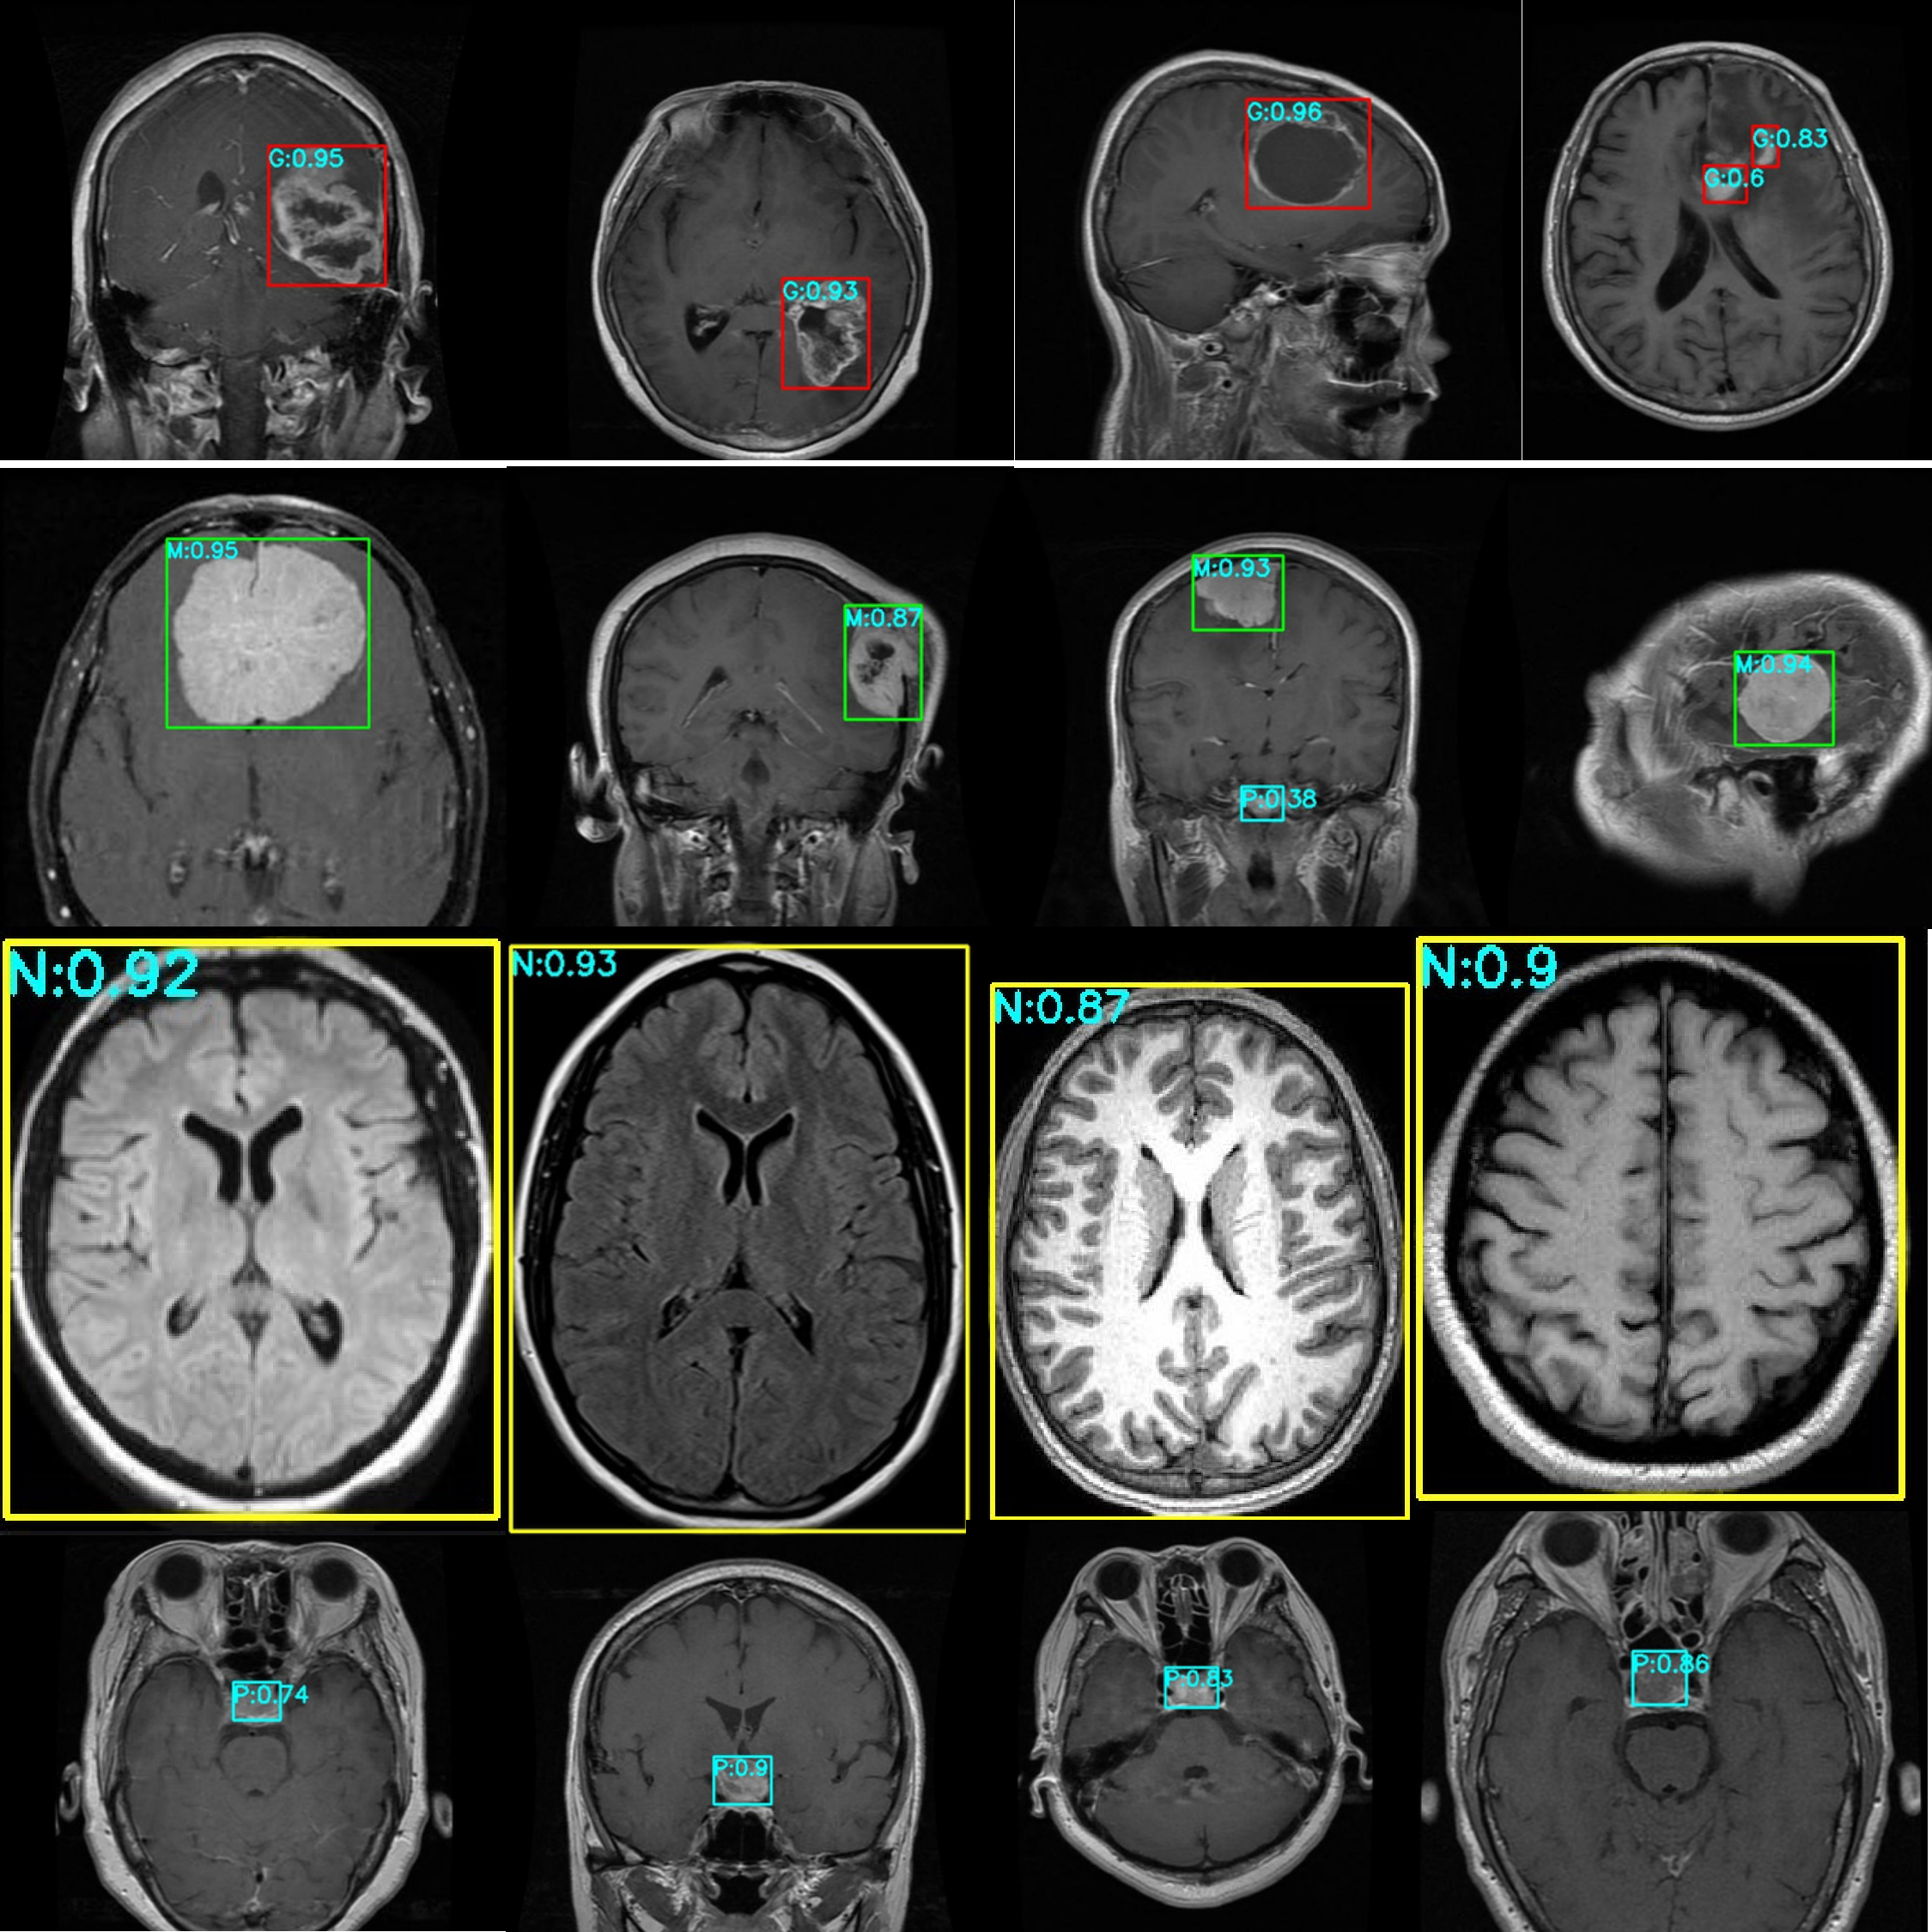

Figure 9 presents the test results for the Kaggle brain tumor dataset. The red box and G represent Glioma, the green box and M represents Meningioma, the yellow box and N represent No tumor, the cyan box and P represents Pituitary. The numbers behind represent the probability value of belonging to this class.

Figure 9

Effect diagram of brain tumor detection on the dataset.